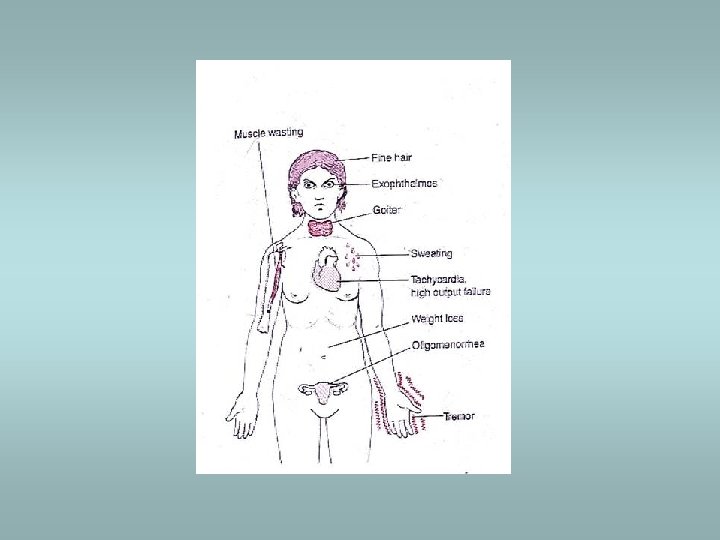

Hyperthyroidism (thyrotoxicosis) ü Increased levels of triodothyronine (T 3), thyroxine (T 4) ü Clinically: wide-eyed gaze, tachycardia, palpitations, nervouseness, weight loss (increased appetite), moist hand, tremor, peripheral vasodilatation ü Associated with diffuse hyperplasia (Graves’ disease) or with toxic multinodular goitre or toxic adenoma ü May be associated with struma ovarii (teratoma)!!